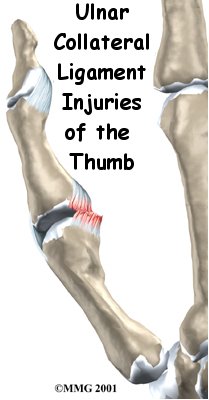

Injury to the ulnar collateral ligament of the thumb is fairly common. This strong band of tissue is attached to the middle joint of the thumb, the joint next to the web space of the thumb. This condition is sometimes called gamekeeper's thumb because Scottish gamekeepers commonly injured their thumbs as a result of their job.

The joint that is affected is called the metacarpophalangeal joint, or MCP joint. Any hard force on the thumb that pulls the thumb away from the hand (called a valgus force) can cause damage to the ulnar collateral ligaments. When the thumb is straight, the collateral ligaments are tight and stabilize the joint against valgus force. If the force is too strong, the ligaments can tear. They may even tear completely. A complete tear is also called a rupture.

When the collateral ligaments actually tear, the MCP joint becomes very unstable. It is especially unstable when the thumb is bent back. If one of the ligaments pulls away from the bone and folds backwards, it won't be able to heal in the correct position. When this happens, surgery is needed to fix the ligament.

Ligament Tear